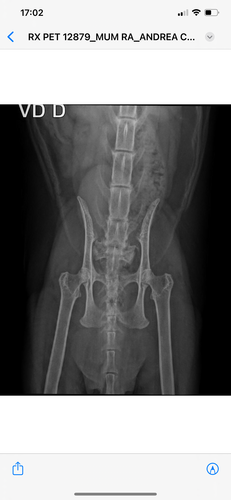

Este acidente ocasionou muitas lesões como: fratura de fêmur, deslocamento de bacia, fratura de cauda e perda de controle fisiológico.

Diante dessa situação, ele terá que passar por uma cirurgia de grande porte para estabilizar sua situação, nesta cirurgia ele colocará pinos na pata e removerá a cauda. Conseguimos um cartão de crédito para pagar as despesas mas está muito caro e precisamos de ajuda!